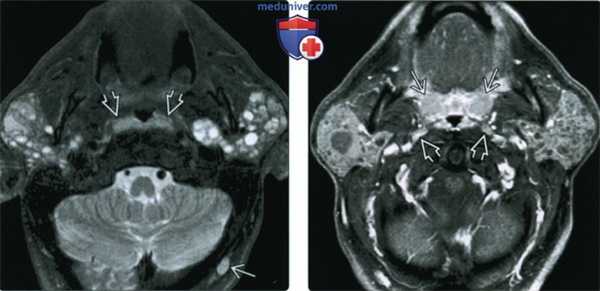

(Слева) MPT STIR, аксиальная проекция. В обеих околоушных железах визуализируются лимфоэпителиальные кисты. Обратите внимание, что вовлечены и поверхностная, и глубокая доли желез. Присутствует реактивная лимфаденопатия затылочных узлов. Гипертрофия небных миндалин незначительная.

(Справа) МРТ Т1ВИ FS c КУ, аксиальная проекция. Двусторонние кистозные и солидные образования у ВИЧ-положительного пациента. Небные миндалины гипетрофированы, также имеет место реактивная лимфаденопатия латеральных заглоточных лимфоузлов.